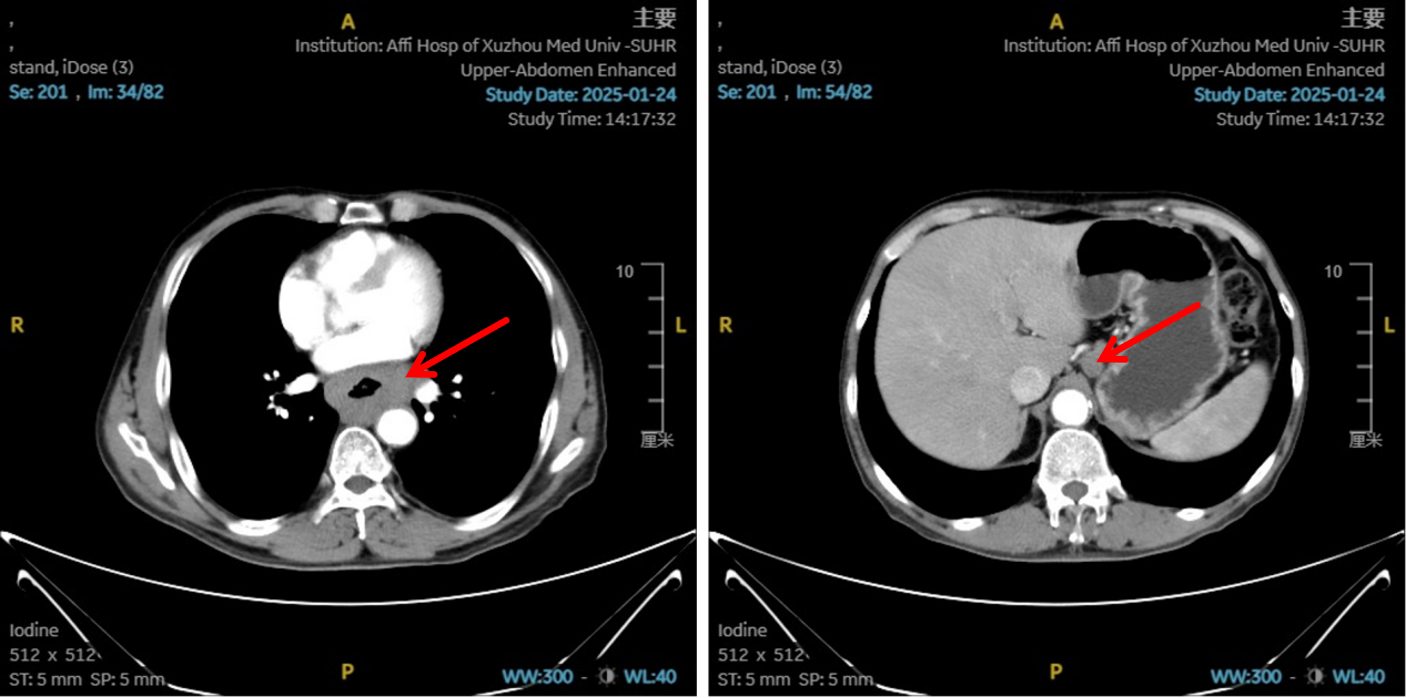

图1:初治影像学 [图左:食管胸中下段管壁增厚,强化不均,较厚处管壁约17mm,边缘模糊,病灶局部与邻近大血管、气管壁分界不清。图右:纵隔内(3P、4、7)、左肺门及胃小弯旁示多发增大淋巴结影,部分融合,强化不均,较大者大小约18mm×15mm。]